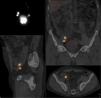

MethodsWe applied the technique to 45 patients. After an intraprostatic injection of 99mTc-nanocolloid and preoperative single-photon emission computed tomography (SPECT/CT), we extracted the sentinel lymph nodes, guided by a portable Sentinella® gamma camera and a laparoscopic gamma-ray detection probe. The eLFD was completed to establish the negative predictive value of the technique.

ResultsSPECT/CT showed radiotracer deposits outside the eLFD territory in 73% of the patients and the laparoscopic gamma probe in 60%. The mean number of active foci per patient was 4.3 in the SPECT/CT and 3.2 in the laparoscopic gamma probe. The mean number of extracted sentinel lymph nodes was 4.3 (0–14), with 26% outside the eLFD territory. The lymph nodes were metastatic in 10 patients (22%), 6/40 (15%) when the prostatectomy was the primary treatment. In all cases with metastatic lymph nodes, there was at least one positive sentinel node. Metastatic sentinel lymph nodes were found outside the eLFD territory in 3/10 patients (30%). The sensitivity was 100%, the specificity was 94.73%, the positive predictive value was 81.81%, and the negative predictive value was 100%.